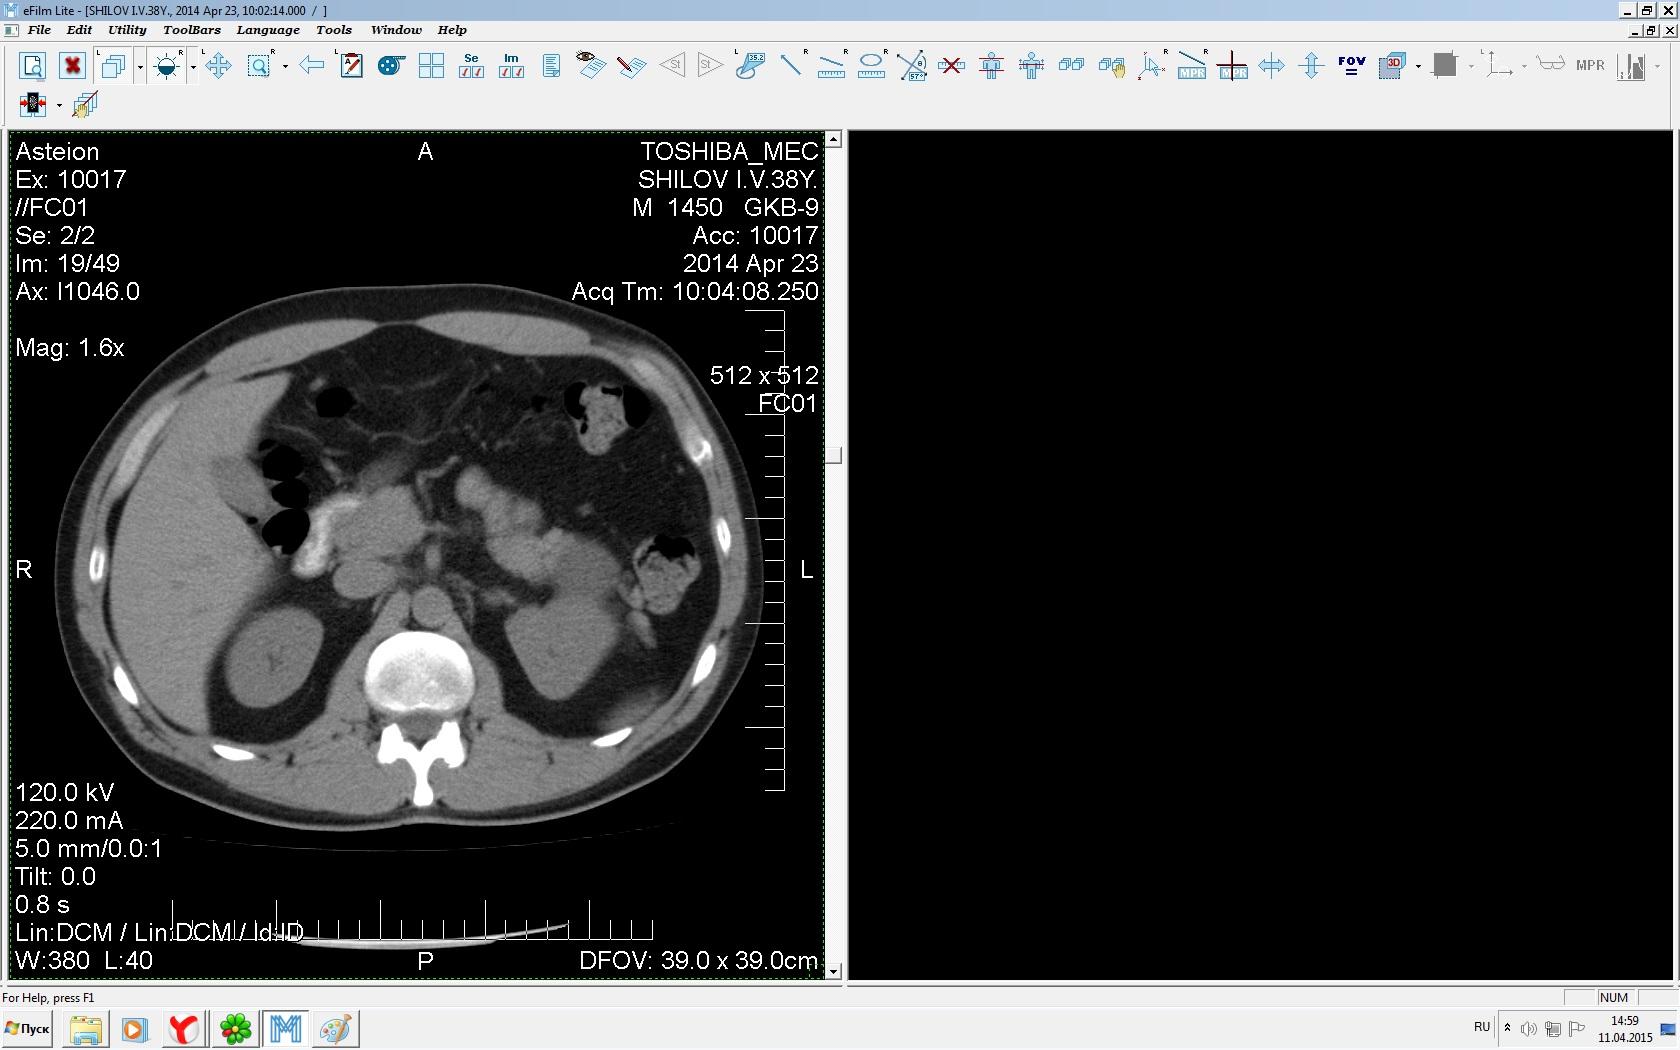

Здравствуйте. У меня киста левой почки. Из заключения: левая почка увеличена, деформирована за счёт наличия в среднем сегменте округлого жидкостного +6, +15 HU образования 66х53 мм, деформирует, поддавливает чаше-лоханочную систему. Сосудистые ножки структурные. В урологии мне сперва предложили лапароскопию, когда я лёг на операцию - изменили на полостную в связи со сложностью. Потом сказали что шансов вырезать кисту без почки практически нет. Даже если кисту удалить чудесным способом, то почка всё равно сложится и не будет работать. В итоге операцию отменили. Скажите, пожалуйста, есть ли современный метод удалить кисту и сохранить почку в моём случае? Томография почки в приложениях. Заранее благодарю.

Эту кисту можно просто пропунктировать, аспирировать и склерозировать - под местной анестезией. Ничего сверхестетственного не определяется по данным КТ. Можете написать мне на почту. aristova-tatyana@mail.ru